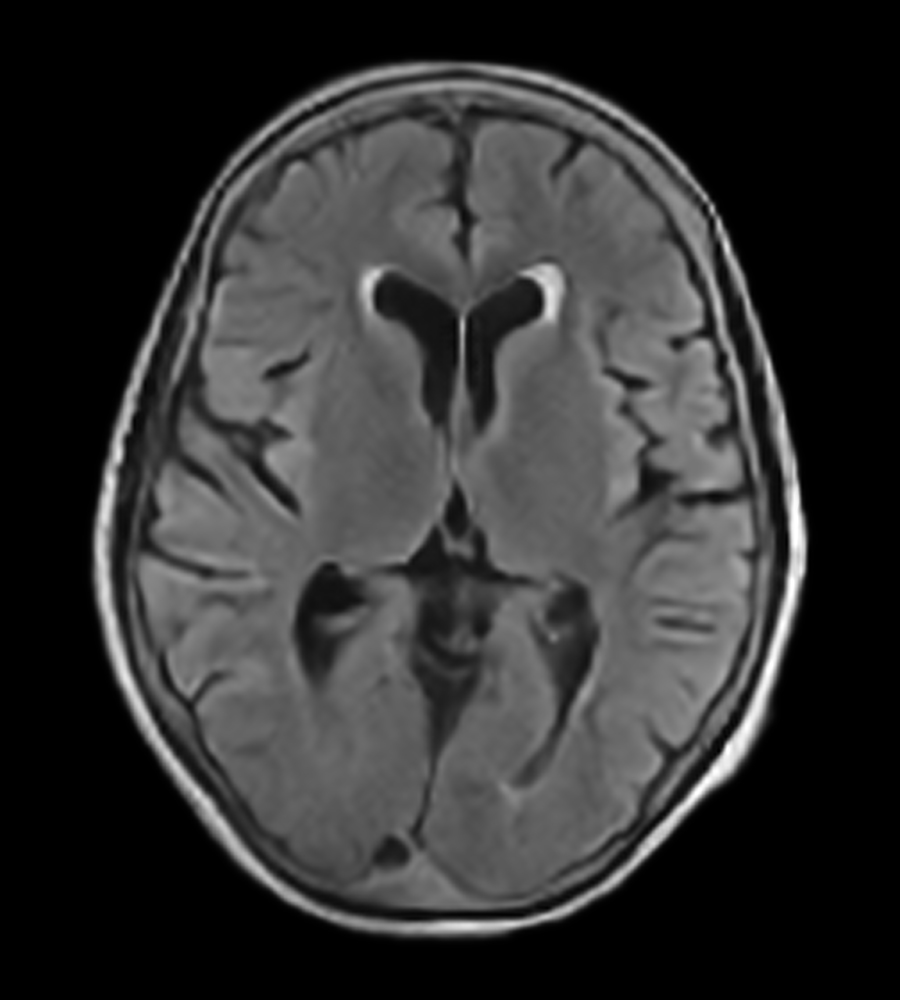

Clinical Images

Clinical Case Types: Headache, Migraine, Multiple Sclerosis, Microvascular Disease, and Tumor Routine Follow-up.

Headache